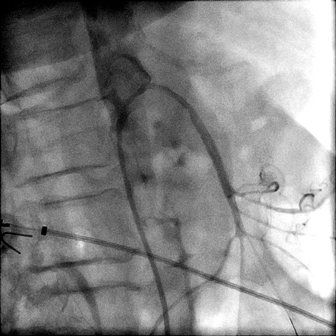

Ангиография. Результат лечения. Верхняя брызжеечная артерия проходима.

После проведенной операции состояние пациентки стабилизировалось, боли в животе прекратились. В данный момент пациентка идет на поправку.